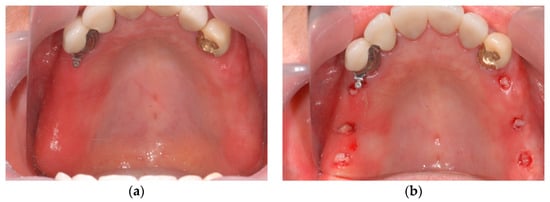

1. Introduction

2.6. Case Study